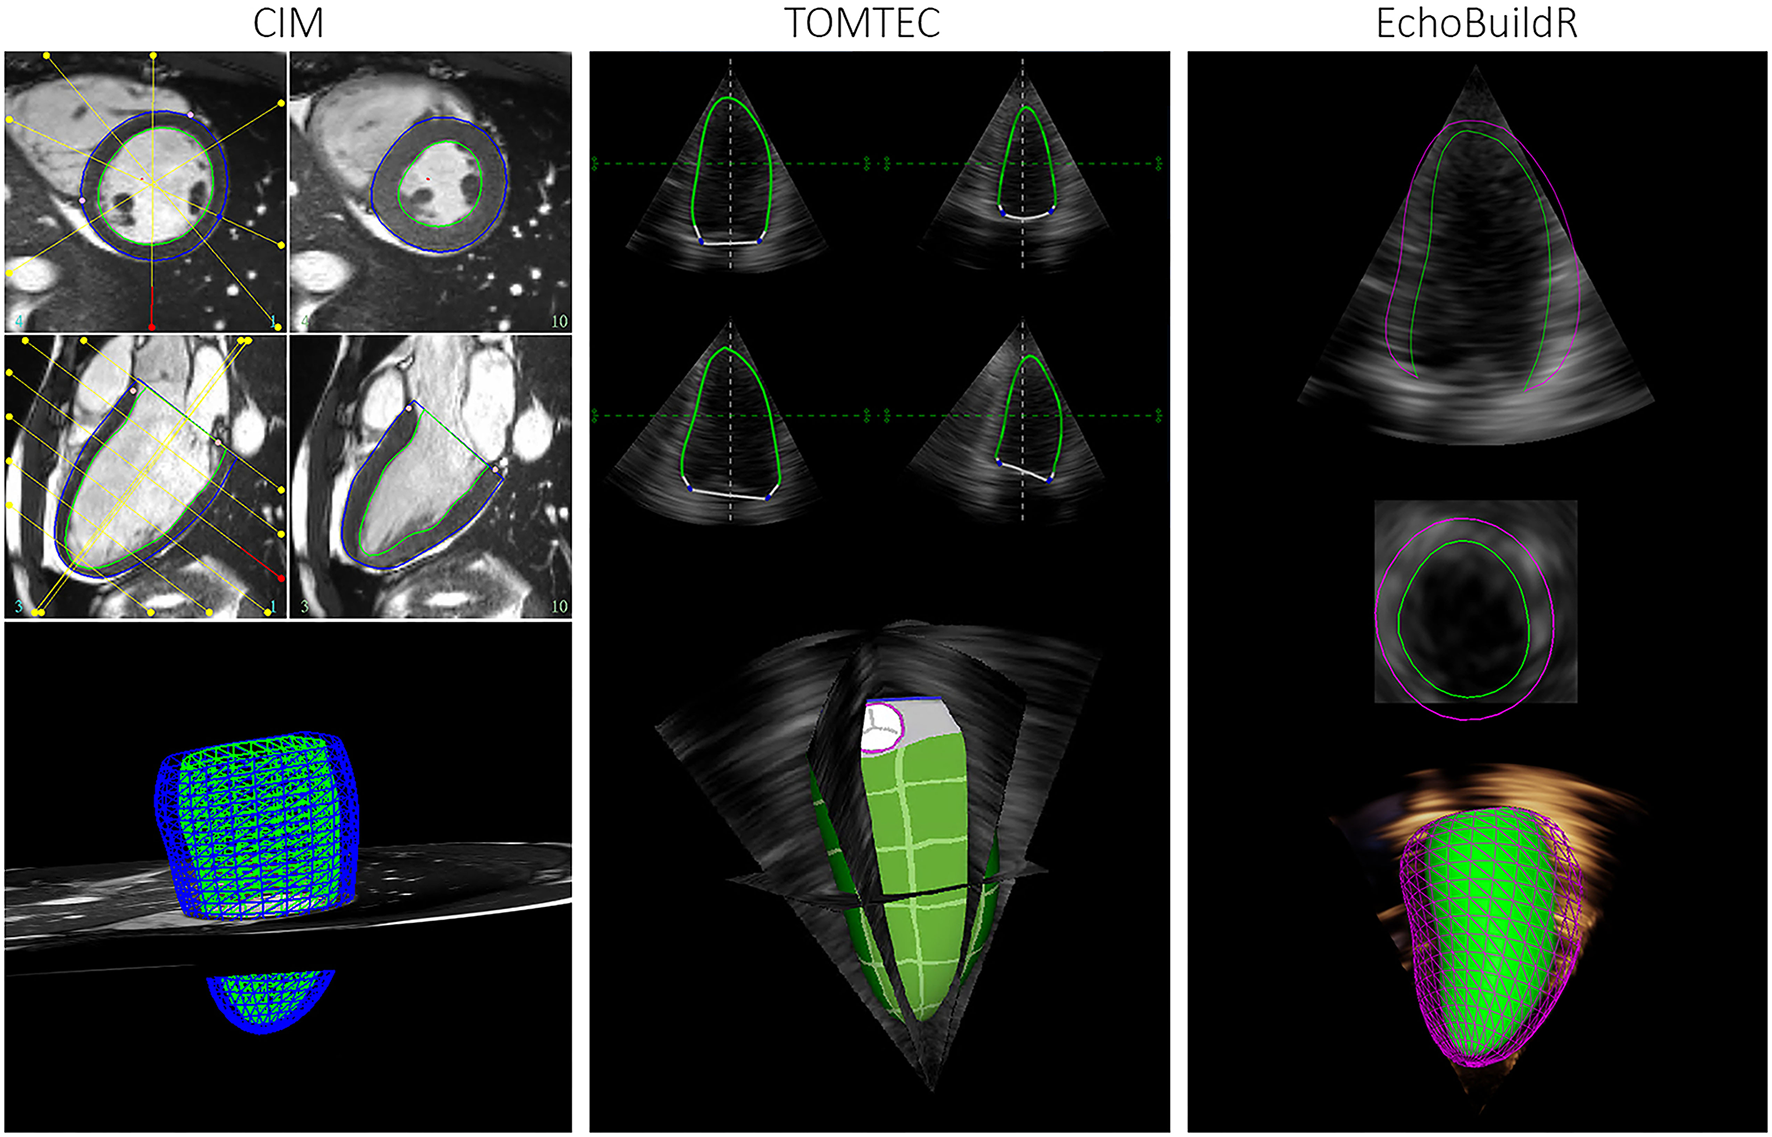

Figure 1

Graphical user interface for semi-automatic construction of LV geometries in CIM (left), TOMTEC (middle), and EchoBuildR (right). (Note that dynamic epicardial modeling was not supported in TOMTEC).

To investigate inter-software variability in 3D-echo LV geometric analysis, three different tools were selected. Two were semi-automatic methods—TOMTEC 4D LV-ANALYSIS 3 (TOMTEC Imaging Systems GmbH, Unterschleissheim, Germany), a commercially available echo analysis software suite; and EchoBuildR 3.4.0 (Siemens Medical Solutions, Mountain View, CA, USA) prototype software based on boundary detectors and a statistical shape model constructed from a large expert-annotated database (13). Left ventricular models were created by interactively manipulating the contours to fit the myocardium, carried out by the same observer (Expert A) in both applications (Figure 1) on separate occasions, after having completed CMR analysis for all participants. To estimate the inter-observer variability associated with 3D-echo, a third observer (Expert C, an experienced clinical cardiac sonographer) repeated the geometric analysis on all 70 subjects using the TOMTEC application.